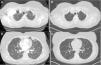

CT of chest (A), initial CT demonstrating left upper lobe nodule with cavitation (B), nine month follow-up CT with resolution of left upper lobe nodule, (C) initial CT demonstrating peripheral nodule in the lingual and (D) nine month follow-up CT with resolution of peripheral nodule in the lingual.

Tumor necrosis factor (TNF) is an overexpressed pro-inflammatory cytokine in RA patients, and the American College of Rheumatology has formal recommendations on the use of anti-TNF biologic agents in RA patients with poor prognostic factors. We report a case of a 50-year-old female developing multifocal nodular consolidations, with and without cavitation (Fig. 1A and C), one month after initiation of etanercept. Immunosuppressive drugs were suspended and a bronchoalveolar lavage of the left upper lobe and lingula were negative for an infectious etiology. Devoid of a confirmed infection, her RA medications were restarted, except for etanercept. Serial CT imaging demonstrated interval regression of the nodules. Radiographic changes were seen at the two-month follow up CT, and have remained unchanged at nine months (Fig. 1B and D).